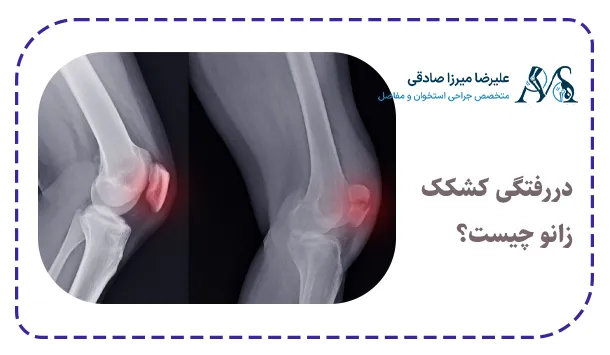

دررفتگی کشکک زانو چیست؟

دررفتگی کشکک زانو یک آسیب مفصلی است که زمانی رخ می‌دهد که کشکک یا همان استخوان کوچک جلوی زانو، از جای طبیعی خود در شیار استخوان ران خارج شود. در حالت طبیعی کشکک داخل یک شیار استخوانی حرکت می‌کند و هنگام خم و راست شدن پا، مسیر مشخصی دارد. اما اگر بر اثر ضربه، پیچش ناگهانی یا ضعف رباط‌ها و عضلات اطراف زانو نیروی غیرعادی به آن وارد شود، کشکک از مسیر خود خارج شده و جابجا می‌شود.

پزشک برای تشخیص این مشکل ابتدا معاینه فیزیکی انجام می‌دهد و موقعیت کشکک را بررسی می‌کند. در بسیاری از موارد برای اطمینان بیشتر از تصویربرداری مانند رادیوگرافی یا ام آر آی زانو  استفاده می‌شود. این تصاویر نشان می‌دهد که آیا کشکک به جای خود بازگشته یا همچنان جابجا مانده است و همچنین وضعیت رباط‌ها و غضروف بررسی می‌شود.